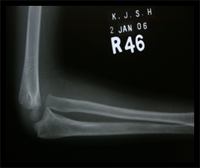

The Monteigga-fracture dislocation is an injury complex where there is fracture of the ulna and dislocation of the radial head. The ulnar fracture may be incomplete or complete and sometimes there is only plastic deformation of the ulna bone. The injury assumes importance due to the frequency with which the radial head dislocation is missed. Acute injuries of the forearm should always be followed by thorough examination of the wrist and elbow.

Biplanar radiographs should include the wrist joint and elbow joint to rule out any joint subluxation or dislocation. Two cases of late presenting Monteigga Fracture — Dislocation. Clinical Features

Open reduction of the radio-capitellar joint with ulnar angulation osteotomy. The ulnar—distraction osteotomy to achieve radial head reduction. No ligament reconstruction was required. Monteigga Fracture – Dislocation.